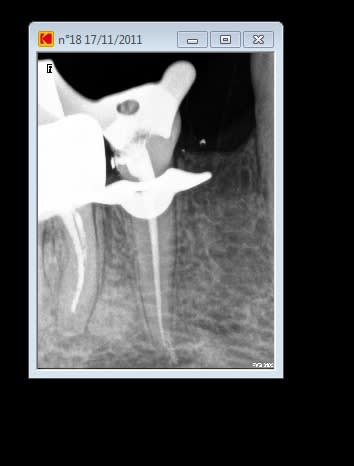

la dent du président

15/11/2011 à 01h11

Content de moi.

Gutt-A

15/11/2011 à 01h23

Tu m'etonnes...avec une racine pareille on se donne tous les moyens pour ne pas avoir a l'extraire un jour...:))

Jolie endo.

En fait, c'est la même endo, le radios ont été interverties la finale a été prise sans clamp.... mais l'endo à été faite sous digue.